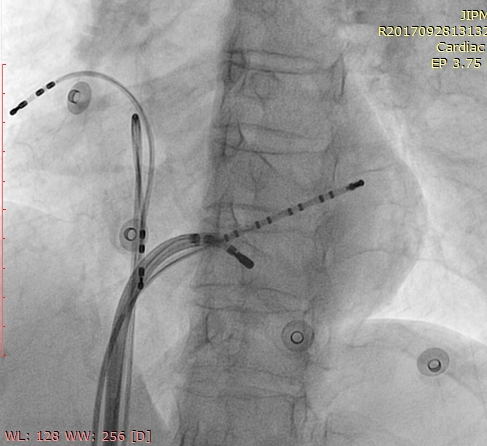

CS venogram

cs_venogram00001.jpg

Successful site

succ_site00001.jpg